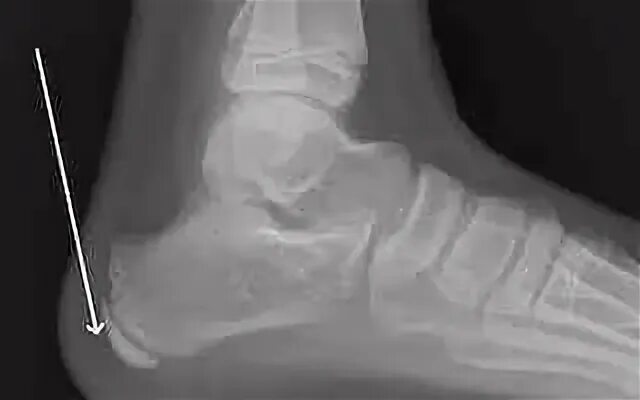

Болезнь шинца у детей код по мкб